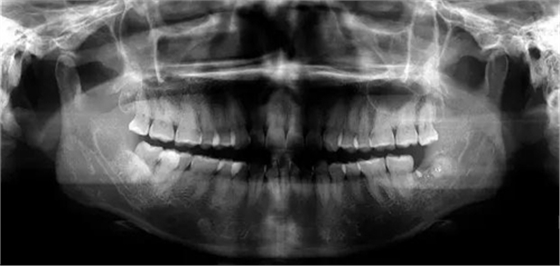

如果斷根在2毫米以?xún)?nèi),而且斷根沒(méi)有根尖周炎。可以不取出,拔牙創(chuàng)口同樣愈合良好,根尖與牙槽骨形成骨性愈合。不會(huì)出現(xiàn)任何并發(fā)癥。特別是在拔除上頜后牙時(shí),根尖接近上頜竇,如強(qiáng)行取出,易造成更大的創(chuàng)傷,另外在拔除阻生第三磨牙時(shí),

如果斷根接近下牙槽神經(jīng)管時(shí),去除時(shí)用力不當(dāng)容易損傷下牙槽神經(jīng),造成下唇麻木。當(dāng)然在下列情況下就一定要取出,所拔的牙有根尖周炎時(shí),如不拔除就要引起感染,斷根不在原牙槽窩內(nèi),也必須取出,否則也易引起感染,且不能形成骨性愈合。

當(dāng)斷根進(jìn)入上頜竇或咽后壁時(shí)一定要取出,否則同樣會(huì)引起感染,腫脹疼痛不能愈合。

遇到斷根怎么辦?我的觀點(diǎn):拔!但有個(gè)前提,必須保證安全,否則寧可保留,因此拔牙前的溝通很重要!